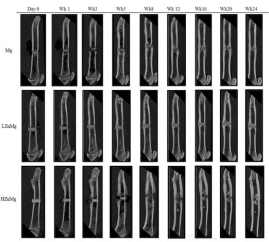

The degradation process of the implant is visualized by 3D reconstruction images, as shown in Figure 1. The differences in the remaining volume and the degradation behaviors were already distinguishable at early stage (1 month) of the experiment. By week 4 there was an obvious volume loss in pure Mg implants [16-20]. The average volume was reduced by an average of 45% from its original volume [21,22]. In comparison, an average loss of only 4% is recorded in LZnMg implants while the structure remained almost unchanged except the formation of small and shallow pits on the surface [23-25]. For the H, Zn, Mg implants, over half of the implant volume was lost within 4 weeks and there was obvious change in implant dimensions. A sharp reduction in implant volume in week 16 was found in Mg group, while fragmentation of implant begins at week 6 in the H, Zn, Mg group. On the contrary, little dimension change could be detected inside LZnMg groups throughout the 24 weeks period. Degradation of LZnMg remained slow throughout the 24 weeks period. There was increasing amounts of small and shallow surface pits with an overall intact structure [26-30]. Overall, the degradation process in pure Mg implants was relatively uniform compared to H, Zn, Mg until the shape decreases in volume after week 12. For H, Zn, Mg, the implants generally disintegrate into small pieces by week 12 and completely degraded within 16 weeks.